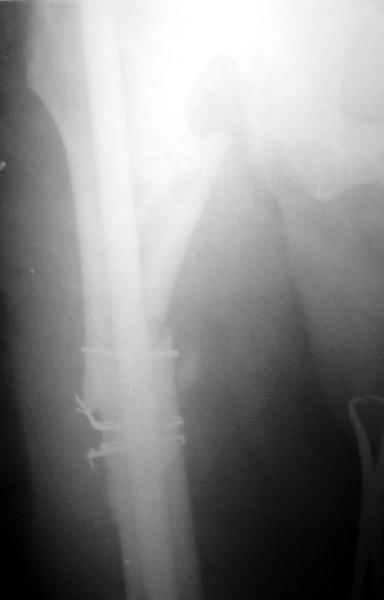

1) Мы бы не убирали проволоку, и вообще не вмешивались открыто на очаге - это ничего не даст, кроме ухудшения кровоснабжения концов отломков. Если просто закрыто перештифтовать при подобной картине, лучше с рассврливанием - это по нашему опыту дает сращение в 100%. В приложении пример - болезненное несращение более года, результат через полгода.

1

2